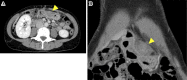

A 44-year-old woman presented to our hospital with abdominal pain. Abdominal ultrasonography and computed tomography showed a mass-like change in the lesser omentum between the liver and stomach. Esophagogastroduodenoscopy revealed a submucosal tumor-like change, and endoscopic ultrasonography (EUS) revealed that the mass was located outside of the stomach wall. We performed EUS fine-needle aspiration and diagnosed panniculitis of the lesser omentum. Based on these findings, we suggest that mass-like lesions in the lesser omentum and submucosal tumor-like changes in the anterior wall on the lesser curvature side of the stomach be evaluated for the possibility of panniculitis of the lesser omentum.